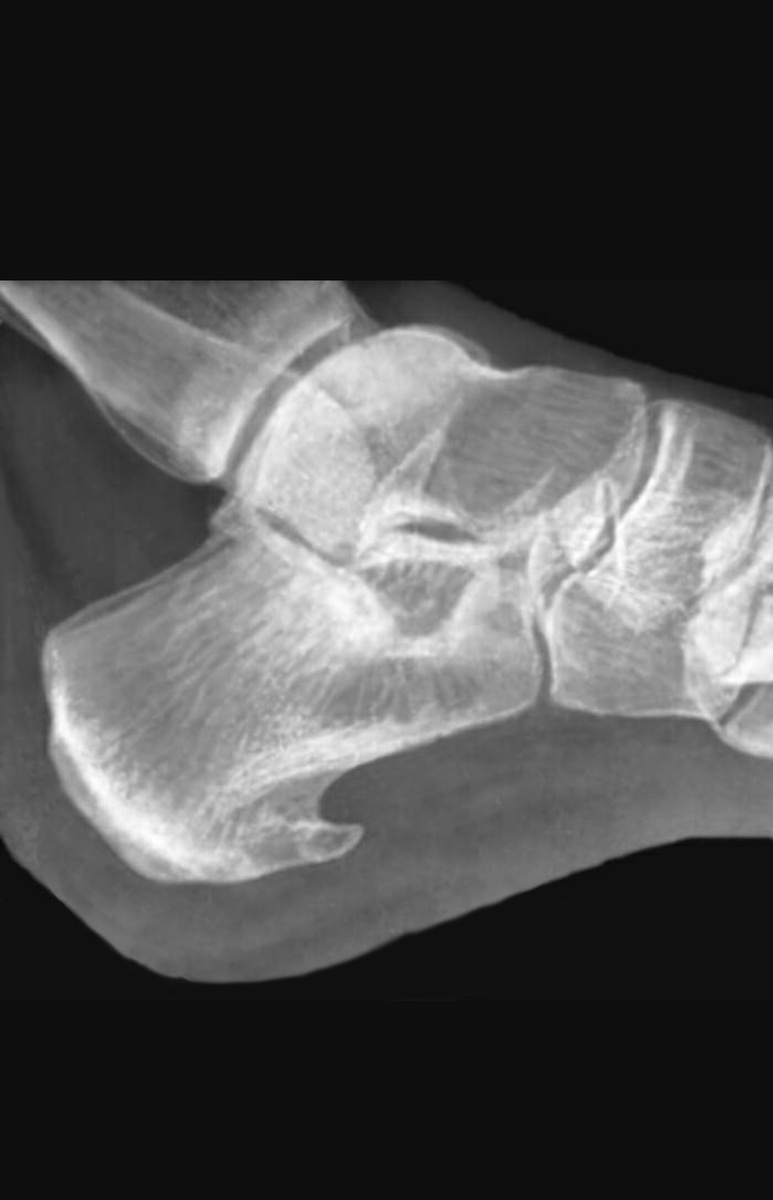

По ощущениям,у меня уже как то так,при чем шип растет вниз...